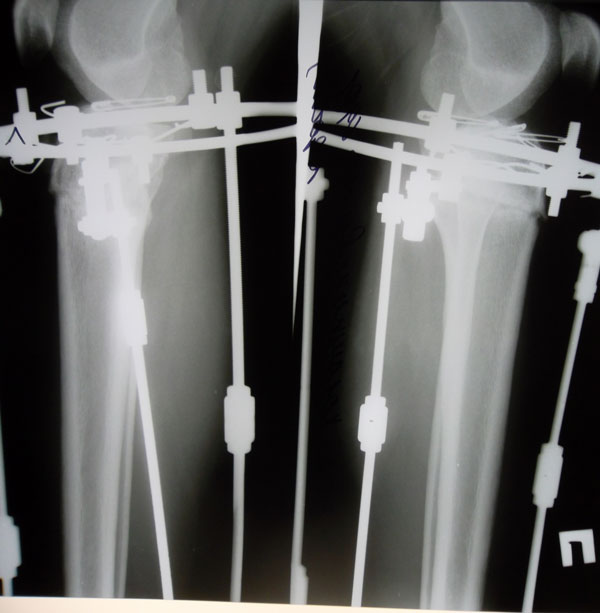

Рентгеновские снимки в прямой проекции.